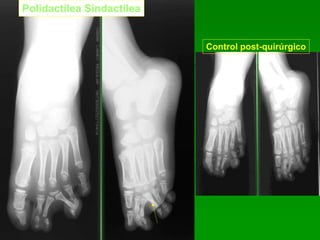

Polidactilea Sindactilea

Control post-quirúrgico